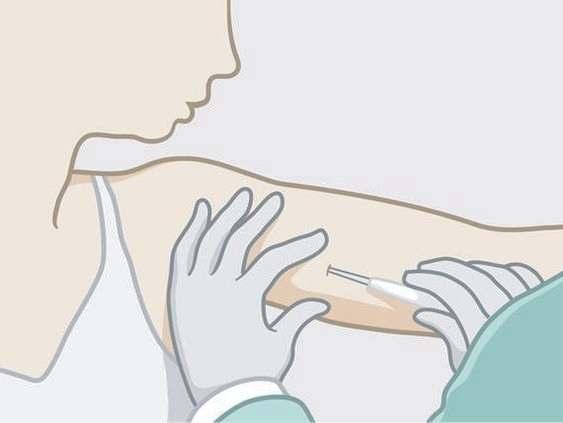

ANTICONCEPTIVO SUBDERMICO

Implante hormonal compuesto por una varilla del tamaño de una cerilla que se coloca bajo la piel del brazo de la mujer, ofreciendo protección anticonceptiva entre 3 y 5 años.

Este método es altamente eficaz, con una tasa de éxito superior al 99%, y dura de 3 a 5 años, sin necesidad de mantenimiento diario, aunque puede causar cambios en los patrones de sangrado menstrual y otros efectos secundarios

Sin embargo, el médico puede retirarlo en cualquier momento y la mujer recuperará la fertilidad en un tiempo mínimo. Eficacia del 99 %, el implante subdérmico es un método anticonceptivoes de larga duración .

Consiste en una pequeña varilla flexible insertada bajo la piel del brazo, la cual libera constantemente la hormona progestina para prevenir el embarazo, su duración varía entre 3 y 5 años